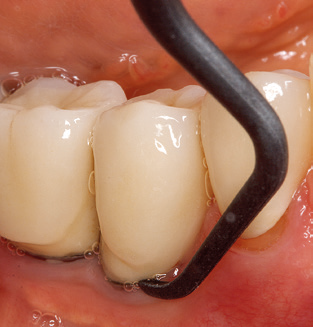

The current working concept for SPT

Updating the patient’s medical history is an important aspect of SPT and should occur at least once per year. It helps the dental team to identify and document any new risk factors. Especially when a patient is treated over many years, it is important to establish whether patient-specific and general health risk factors have changed. This primarily concerns a heightened risk as a result of diabetes, but other general conditions (cardiovascular disease and neoplasia) can also produce a modified risk profile as a result of the treatment performed and medication administered. Accordingly, updating the medical history as part of SPT is very important, as a modified risk profile may trigger the need to adapt the treatment interval. In the next step, it is important to afford the diagnostics due attention. Whilst instruments are a central aspect of SPT, findings and their documentation must never be neglected. The periodontological findings are essential for a good diagnosis; increases in the pocket depths and the BOP index are clear indicators of advancing periodontal and peri-implant disease. As such, the team should not shy away from probing implants too, with the aim of gathering the requisite data. At the same time, it is important to use periodontal probes with millimetre markings. Metallic probes have already been used for determining pocket depths around natural teeth for decades. In the case of implants, the challenge of recording correct and reproducible pockets depths is even greater. As the discrepancy between the implant diameter and the contour of the superstructure regularly results in overcontouring of the superstructure, flexible probes which still feature millimetre markings are a sensible solution for measuring pocket depths around implants (e.g., Colorvue Kit PCV11KIT6, HuFriedy; Fig. 4).